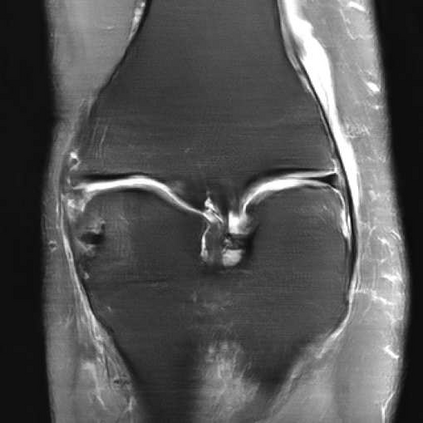

Deep Learning (DL) methods have shown promising results for solving ill-posed inverse problems such as MR image reconstruction from undersampled $k$-space data. However, these approaches currently have no guarantees for reconstruction quality and the reliability of such algorithms is only poorly understood. Adversarial attacks offer a valuable tool to understand possible failure modes and worst case performance of DL-based reconstruction algorithms. In this paper we describe adversarial attacks on multi-coil $k$-space measurements and evaluate them on the recently proposed E2E-VarNet and a simpler UNet-based model. In contrast to prior work, the attacks are targeted to specifically alter diagnostically relevant regions. Using two realistic attack models (adversarial $k$-space noise and adversarial rotations) we are able to show that current state-of-the-art DL-based reconstruction algorithms are indeed sensitive to such perturbations to a degree where relevant diagnostic information may be lost. Surprisingly, in our experiments the UNet and the more sophisticated E2E-VarNet were similarly sensitive to such attacks. Our findings add further to the evidence that caution must be exercised as DL-based methods move closer to clinical practice.